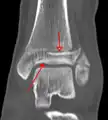

A triplane fracture of the ankle as seen on CT